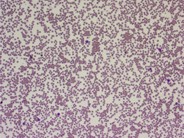

Cold agglutinin disease may be rare but there are others out there who are finding ways to manage life with the disease. Cold agglutinin disease is a rare and poorly understood disorder affecting 15 of patients with autoimmune hemolytic anemia. When affected peoples blood is exposed to cold temperatures 32º to 50º F certain proteins that normally attack bacteria IgM antibodies attach themselves to red blood cells and bind.

Cold agglutinin disease is a rare type of autoimmune hemolytic anemia in which the bodys immune system mistakenly attacks and destroys its own red blood cells. The IgM protein fixes complement to the red cell surface. Cold agglutinin disease is a form of direct extravascular antiglobulin-positive hemolysis.

Cold agglutinin disease is a rare and poorly understood disorder affecting 15 of patients with autoimmune hemolytic anemia. Patients with CA but without evidence of cold hemagglutinin disease can safely undergo normothermic cardiopulmonary bypass at 37C and warm cardioplegia without further testing. The pathophysiology is an IgM protein which can be monoclonal cold agglutinin disease or polyclonal usually post-infectious.